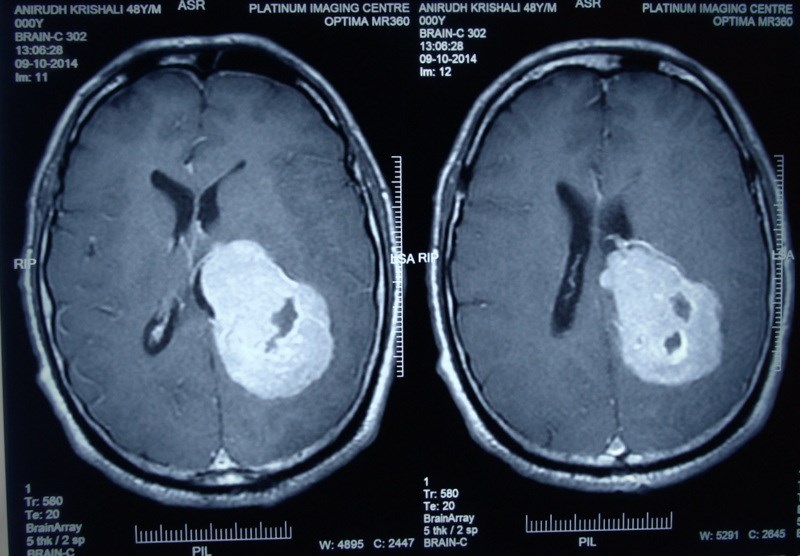

Gliomas

Gliomas are brain tumors that arise from the supporting cells of the brain (‘glia’). These can be diffuse, involving large area of the brain or may be localized. They can be low grade (benign behavior), or high grade (malignant). They often present with headache, neurological weakness, etc and require early surgery for diagnosis, reduction of tumor mass, often followed by radiotherapy and chemotherapy.